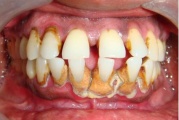

- igemed veritsevad (19)

- igemed punetavad (21)

- ige on paistes (mädapunn)

- igemed on tursunud/vohavad (17)

- igemetaskust eritub mäda (3)

- halb hingeõhk / suu haiseb (12)